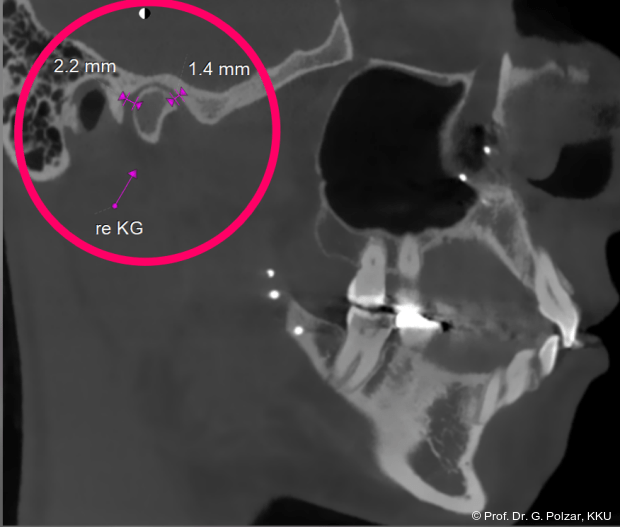

Im Sagittalschnitt zeigen beide Kiefergelenke eine deutlich anteriore Position. Der dorsokraniale Abstand betrug rechts 7,0 mm und links 5,8 mm. In der PEP waren sie im lateralen Bereich ca. 1 mm kleiner als in der Mitte der Sagittalprojektion (Abb. 6a–d).

Beide Kiefergelenke (KG) befinden sich nun in zentraler Kondylen-/Fossa-Position bei neu­traler Okklusion (Abb. 10+11).

Nach der Umstellungsosteotomie mit der UK-­Vorverlagerung kann die Patientin besser zubeißen. Bei maximaler Interkuspidation in neutraler Okklusion befinden sich nun beide Kiefergelenke in zentraler Po­sition zur Gelenkpfanne. Der geringe Abstand des Caput mandibulae zur Schädelgrube lässt auf eine Diskusverlagerung schließen (Abb. 20a+b).